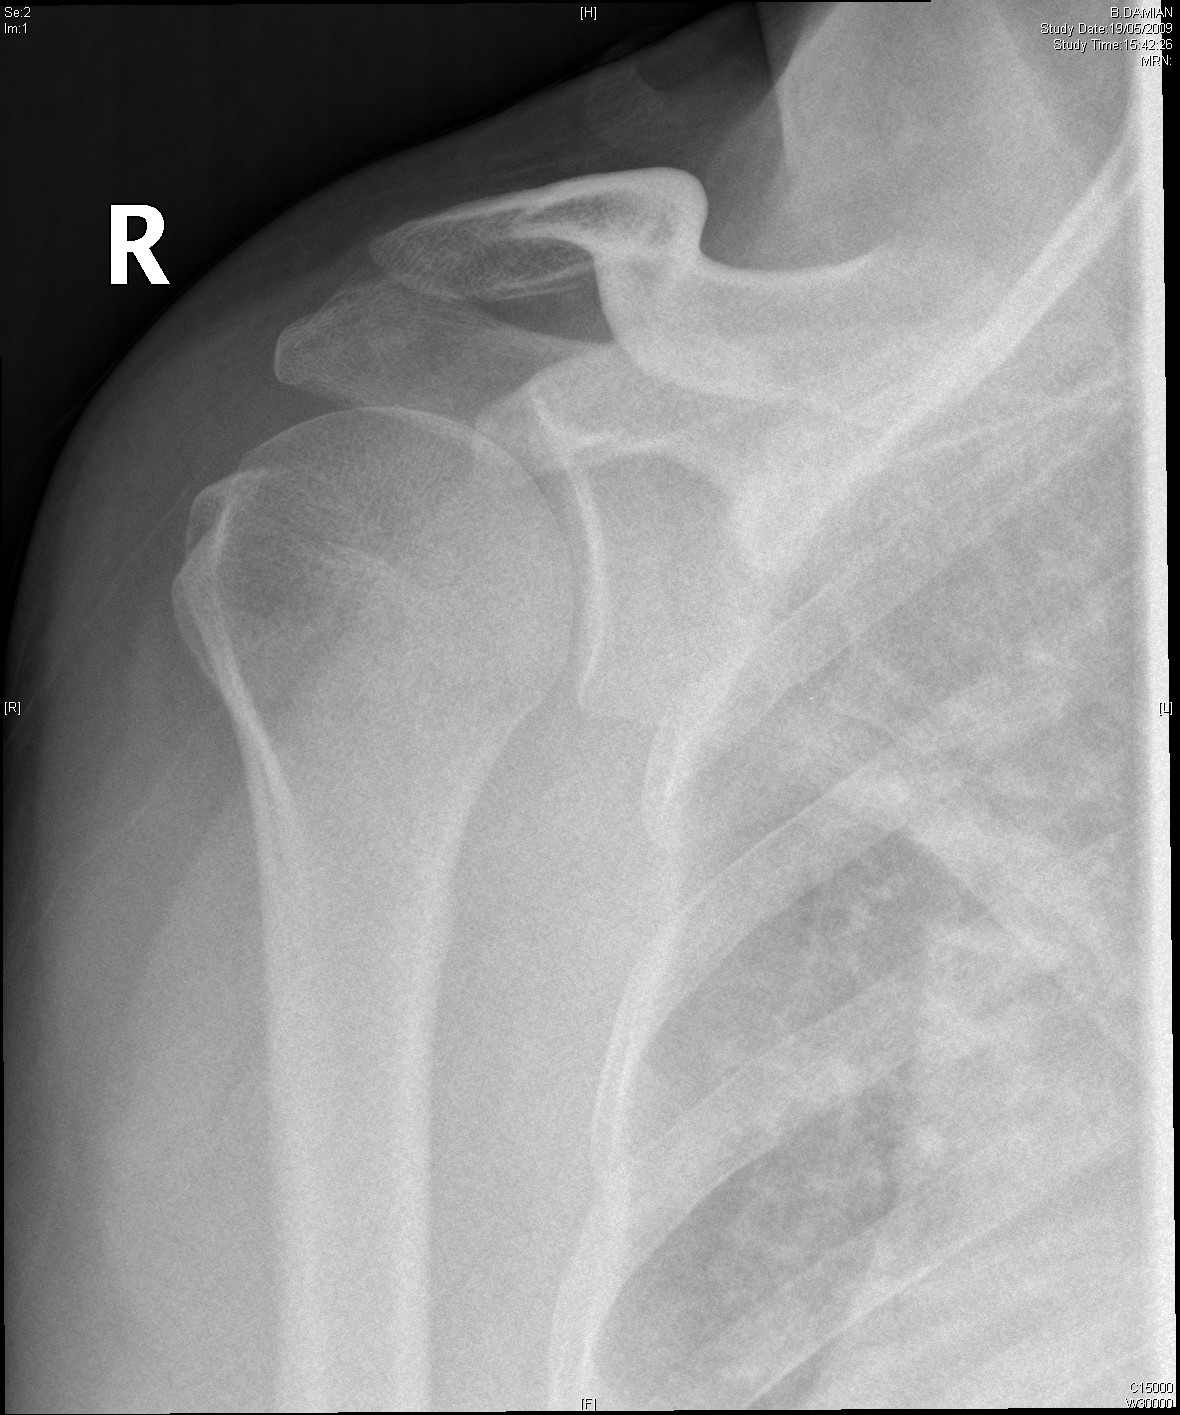

Normal Shoulder

The normal shoulder has several layers.These layers mean that the shoulder joint is several centimeters below the skin. Swelling in the shoulder is not easily seen unless it is very severe.

Beneath all these layers lie the cartilage covered bones of the shoulder joint formed by the humeral head (top of the humerus) and the glenoid (the oval joint surface of the scapula). Arthritis in the bones of the shoulder joint results in loss of the white shiny and smooth articular cartilage leaving the much rougher bones directly in contact with each other.